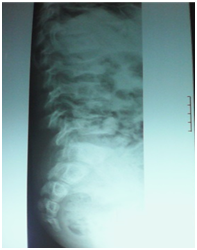

A 12-year-old boy was diagnosed with Sickle Cell Disease (SCD) with genotype SS about one year prior to. He presented with 2 months history of inability to walk and pain in both legs to Komfo Anokye Teaching Hospital in Kumasi, Ghana. The complaints were associated with marked weight loss and generalized body pain. He had been admitted about 2 weeks prior to the onset of current symptoms on account of abdominal pain and anaemia where he was haemo-transfused, given medications and subsequently discharged. There were no other significant findings in the past medical history, immunization history, nutritional and developmental histories. On examination he was found to be wasted (Weight for Height z-score <-3SD), pale, afebrile and anicteric. He had palpable axillary and inguinal lymph nodes (each measuring about 1cm to 1.5cm, mobile, non-tender and not matted). Vital signs were normal on admission. Other significant examination findings were obvious swelling of the right leg which was warm to touch, erythematous and tender on palpation. He had a gibbus deformity of the lower thoracic spine with no remarkable neurological findings in the lower limbs. A diagnosis of SCD with vaso-occlusive crises and cellulitis of the right leg was made with differential diagnosis of osteomyelitis, Deep Vein Thrombosis and Potts disease. Initial investigations revealed WBC of 13.51 X 109/dl with Neutrophils 8.83 (65.3%) Lymphocytes 4.27 (31.6%) and Monocytes 0.25(1.9%), Hemoglobin 7.1g/dl, MCV-70.7, MCH-22.4, Platelets: 538, ESR-117, INR-1.05, Prothrombin Time-14.3secs and blood sugar-6.5mmol/L. Malaria parasites were not seen on the blood smear and patient was negative for Retro-Viral Screen for HIV. Other investigations included Doppler Ultrasound, Chest X-ray, Pelvic x-ray, Thoraco-lumbo-sacral spine X-ray (Figure 1-10). Blood culture and sensitivity could not be done at the time of admission as microbiology service in the hospital had a brief logistic challenge. Radiological findings revealed the following: Reduction in the vertebral body heights of T7-T10 with associated reduction in the intervertebral disc spaces and crowding of the posterior ribs. A paravertebral soft tissue mass extending from T4 vertebral level to T11. Coarse trabeculation and sclerosis of the ribs noted. Expansion of the anterior end of the left 8th rib with ill-defined lytic areas. Buckling of the cortex of the lateral aspect of the left 9th rib, suggestive of a fracture. The imaged portion of the proximal humerus shows periarticular osteopenia. Also noted was relatively small left humeral head with left glenohumeral joint space. There are patchy homogenous opacities in both lung fields predominantly in the lower zones. There was associated silhouetting of the hemi diaphragms bilaterally and the cardiac shadow. There was generalized sclerosis of the imaged pelvic bones with coarsening of the trabeculae. The right femoral head was deformed and expanded with sclerosis and lytic areas within. There was associated narrowing of the right hip joint space. The left femoral head also showed patchy lucencies. No deformity of the left femoral head seen. The left hip joint space appeared normal. Also noted was fusion of the sacroiliac joints bilaterally. There was diffuse sclerosis of the imaged vertebrae with coarse trabeculae. The vertebral endplates of L1/L2 and L3/L4 showed sharp depression at the margins with a flat base centrally giving it the H shaped appearance. Also noted were ill-defined lytic areas in the L3 to L5 vertebrae with associated end plate irregularities and reduced intervertebral disc spaces at L3/L4 and L4/L5. No paravertebral soft tissue mass seen. No fracture or listhesis seen. Changes of the thoracic spine were described under the chest x-ray.

These radiological diagnostic features were suggestive of sickle cell disease with Thoracolumbar spondylodiscitis, likely pyogenic; Bilateral Avascular Necrosis of the femoral head (early on the left); Septic arthritis of the right hip and left shoulder joint; Osteomyelitis of the left 8th and 9th ribs. Doppler Ultrasound of the lower limb revealed the following: The right common femoral and superficial femoral veins were of normal lumen with good wall to wall compressibility, good colour doppler and spectral wave form properties. The right popliteal and posterior tibial veins however showed extensive echogenic intraluminal-filling defect with resultant loss of wall-to-wall compressibility (percentage stenosis 76%). The accompanying arteries were of normal size and caliber and showed good colour doppler and spectral properties. There was thickening of the subcutaneous tissue with dilated fluid channels seen in the right foot. Inguinal as well as popliteal lymph nodes with retention of their fatty hilum noted averaging 0.9*0.5cm. Also noted was a 1.4*0.9*1.5cm (volume about 1.0ml) anechoic collection with low-level internal echoes at the medial aspect of the proximal thigh muscles; suggestive of inflammatory changes. Based on the Doppler findings a clinical diagnosis of Right Popliteal and Posterior Tibial Vein Thrombosis with Pyomyositis in a Sickle Cell Disease patient was considered and patient was subsequently administered subcutaneous Enoxaparin 40mg daily as well as Warfarin 3mg nocte, IV Clindamycin 150mg qid, IV Ciprofloxacin. After 2 days of Warfarin and Enoxaparin, INR and PT were repeated and results were 1.1 and 15.1s respectively. The child was followed up closely for four weeks and subsequently discharge. A repeat Doppler finding revealed a completely resolved thrombus with no evidence of DVT.